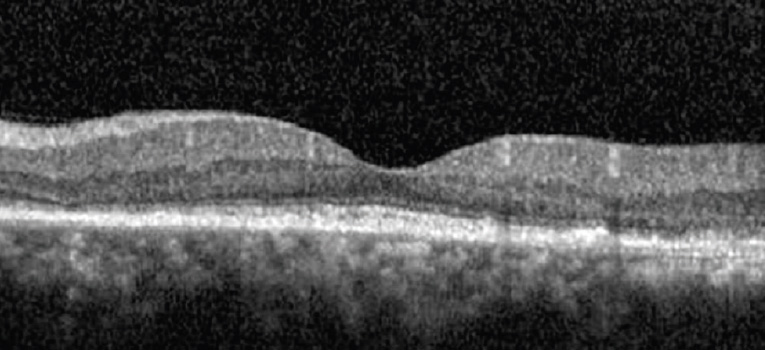

Die Fovea Friendly™ MicroPulse® Lasertherapie erlaubt auch die Behandlung von schwierigen Fällen, in denen die Fovea mit involviert ist. Nach einer MicroPulse® Laserbehandlung kommt es zu keinen morphologischen Veränderungen, der Zerstörung von neurosensorischen Netzhautschichten, weder im OCT, der Angiographie, Autofluoreszenz, oder im Funduskop, nachweisbar. Es entstehen keine typischen Lasernarben und Skotome mit entsprechenden Visus-Beeinträchtigungen.

VA 20/25 CMT 204μm

MicroPulse® Laser Behandlung über der Fovea nach chronisch bullöser RCS. Keine Zerstörung von neurosensorischen Netzhautschichten, keine Lasernarben-Skotome

Lasern über der Fovea ist mit dem Iridex MicroPulse® Laser sicher und kann bei entsprechender Indikation mit in die Behandlung eingeschlossen werden (FDA-zugelassen). Die thermische Stimulation des RPE dient als biologischer Schlüsseltrigger für den Abbau von Flüssigkeitsansammlungen einer ödematösen Retina. Entstehende Heat Shock Proteine haben eine stimulierend proliferierende und protektive Wirkung und bewirken eine „Upregulation“ von angiogenen Inhibitoren sowie eine „Downregulation“ von VEGF.